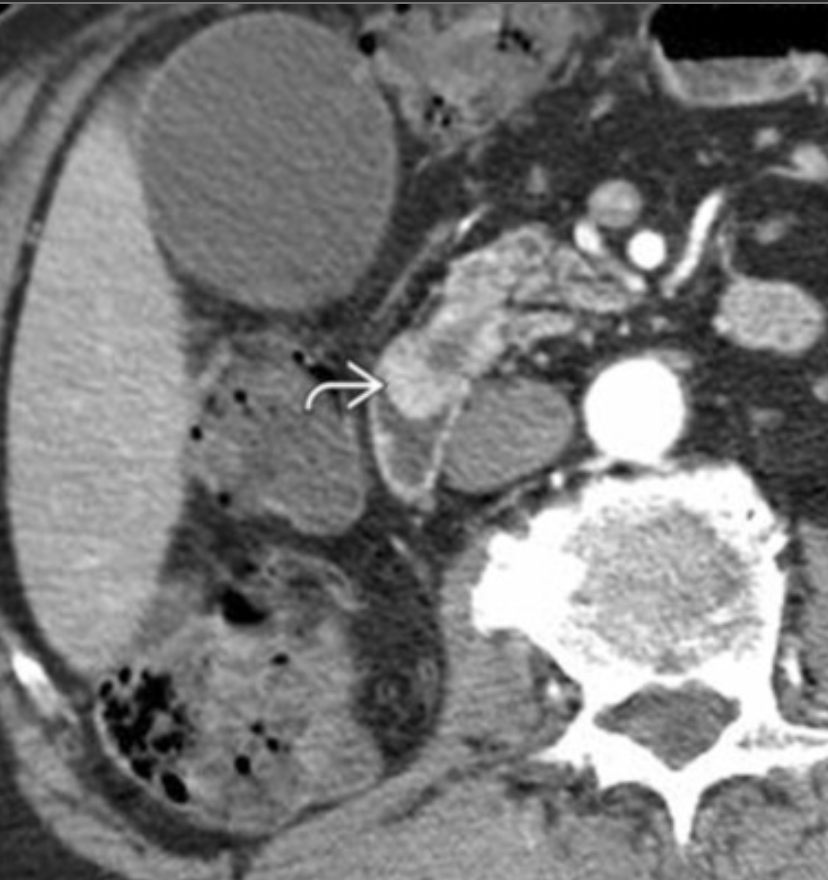

Dilated ducts Dx

Dx?

Dx: type 4A choledochal cyst.